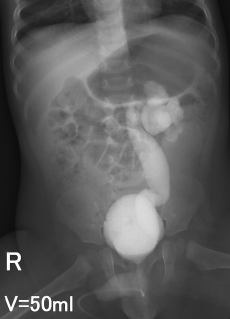

Рефлюксирующий мегауретер: Визуализация и медицинские изображения

Раздел: Фотопуть к знанию